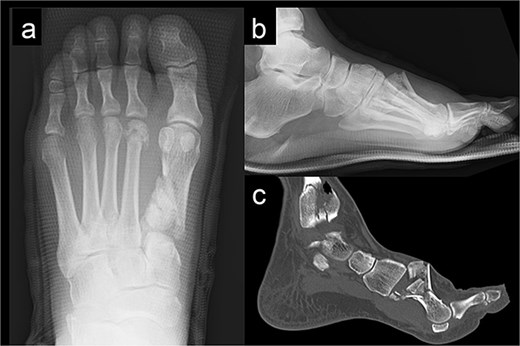

The external fixator was removed 4 weeks after the first surgery. Full weight-bearing was allowed 6 weeks after the operation. The plate was removed after confirming bone union. The patient was able to return to agricultural work 6 months postoperatively, and the American Orthopedic Foot and Ankle Society score 1 year post-surgery was 84. The follow-up radiography image taken at this stage is shown in Fig. 4.